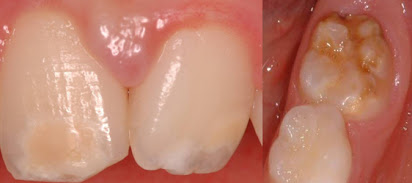

- Infiltrazione di resina e miglioramento estetico dei denti anteriori affetti da ipomineralizzazione molare-incisiva. Valutazione dell'efficacia dell'infiltrazione di resina nel migliorare l'aspetto estetico dei denti anteriori affetti da ipomineralizzazione molare-incisiva. Odontoiatria33 - 1 ott 2024

- Ipomineralizzazione molari-incisivi: ecco i probabili fattori eziologici. Una revisone sistematica ha fatto il punto sui fattori eziologici chiamati in causa nei processi di ipomineralizzazione pre-eruttiva di molari e incisivi (Mih). I più probabili sono ipossia perinatale, infezioni di varia natura, episodi febbrili e malattie renali.

- MIH, una problematica che può incidere molto sulla vita dei pazienti. La Molar and Incisor Hypomineralization è un difetto qualitativo dello smalto: una revisione sistematica indaga il miglior management per questo quadro clinico.